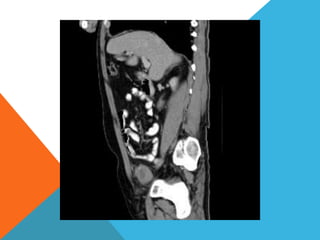

El paciente presentó síntomas de sangrado digestivo y pérdida de peso. Exámenes revelaron gastritis crónica asociada a H. pylori. Un tumor fue descubierto en una colonoscopia normal. La cirugía removió un tumor fibroide solitario, una rara neoplasia mesenquimal que usualmente crece lento y tiene bajo potencial de malignidad. El pronóstico después de la remoción quirúrgica es generalmente bueno.